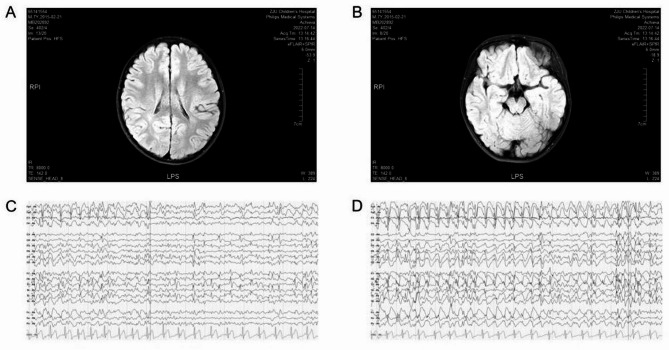

The TBL1XR1 gene (Transducin beta-like 1X-linked receptor 1) is responsible for encoding the TBL1XR1 protein, an important component of the NCoR and SMRT corepressor complexes. 48 missense variants of the TBL1XR1 gene have been reported, which are associated with various phenotypes of neurodevelopmental disorders, including West syndrome, Pierpont syndrome, and others. However, given the important role of TBL1XR1 in neurological diseases, it is still necessary to further explore the variation of TBL1XR1. In this study, we present two patients with distinct variants and phenotypes. Patient 1 exhibits global developmental delay, intellectual disability, delayed language development, and seizures. While patient 2 displays mild facial dysmorphism, significant developmental delay, feeding difficulties, and increased muscle tone. Through trio whole-exome sequencing, two novel pathogenic variants in the TBL1XR1 gene were identified: A heterozygous NM_024665.6:c.940G > T (p.Val314Phe) variant in patient 1 and a heterozygous NM_024665.6:c.1387G > T (p.Asp463Tyr) in patient 2. Discovery of these two novel variant sites expands the mutation spectrum associated with the TBL1XR1 gene.